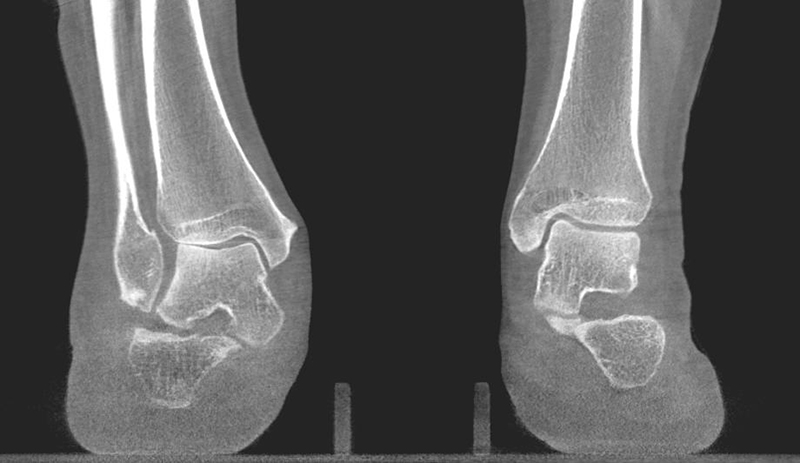

Der Computertomographie (CT) fehlt ebenfalls die Fähigkeit, den Knorpel direkt zu bewerten. Mit dem CT können jedoch weitere Details der knöchernen Verletzung, wie Größe, Form, Umfang und evtl. Dislokation der Läsion beurteilt werden 11. Insbesondere kleine Knochenkanten oder Gelenkkörper lassen sich in der CT wesentlich besser darstellen als mit einem MRT.

Zur Vollansicht und zum Lesen der Bildbeschreibung bitte das Bild anklicken.

In den letzten Jahren hat die digitale Volumen Tomografie (DVT) erheblich an Bedeutung gewonnen. Der Vorteil dieses Verfahrens ist eine computertomografieartige Abbildung unter Vollbelastung des Fußes mit der Möglichkeit einer 3-D Rekonstruktion. Verglichen zur Computertomografie hat die DVT eine deutlich geringere Strahlenbelastung 12. Aus dem Datensatz lassen sich Projektionsbilder errechnen, sodass viele belastete konventionelle Aufnahmen durch eine DVT überflüssig werden.